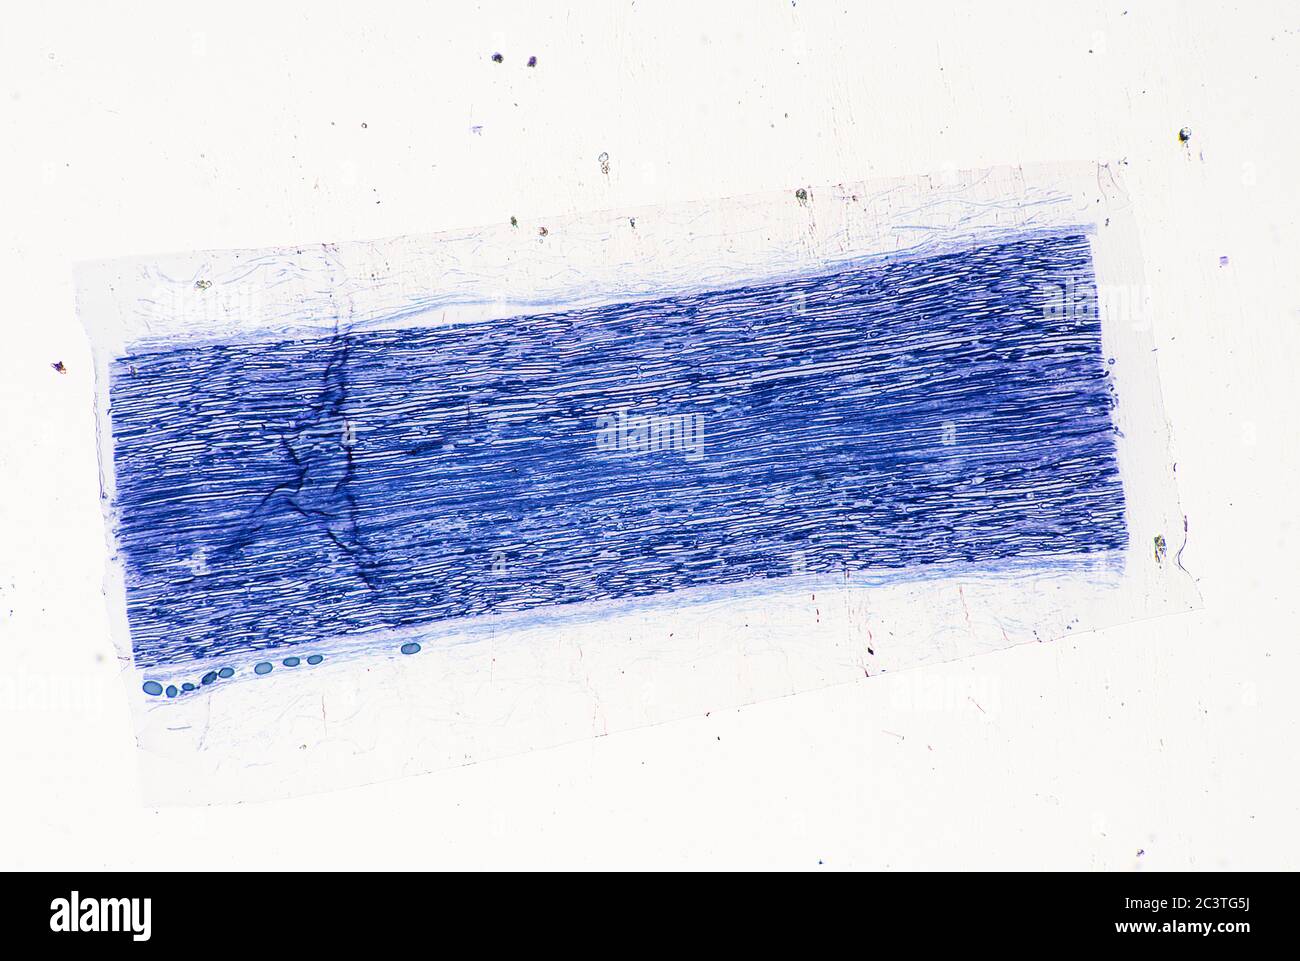

Nerf sciatique mammifère, coupe transversale longitudinale, vue au microscope Banque D'Imageshttps://www.alamyimages.fr/image-license-details/?v=1https://www.alamyimages.fr/nerf-sciatique-mammifere-coupe-transversale-longitudinale-vue-au-microscope-image363801246.html

Nerf sciatique mammifère, coupe transversale longitudinale, vue au microscope Banque D'Imageshttps://www.alamyimages.fr/image-license-details/?v=1https://www.alamyimages.fr/nerf-sciatique-mammifere-coupe-transversale-longitudinale-vue-au-microscope-image363801246.htmlRM2C3TG5J–Nerf sciatique mammifère, coupe transversale longitudinale, vue au microscope

Nerf sciatique mammifère, coupe transversale longitudinale, vue au microscope Banque D'Imageshttps://www.alamyimages.fr/image-license-details/?v=1https://www.alamyimages.fr/nerf-sciatique-mammifere-coupe-transversale-longitudinale-vue-au-microscope-image363801254.html

Nerf sciatique mammifère, coupe transversale longitudinale, vue au microscope Banque D'Imageshttps://www.alamyimages.fr/image-license-details/?v=1https://www.alamyimages.fr/nerf-sciatique-mammifere-coupe-transversale-longitudinale-vue-au-microscope-image363801254.htmlRM2C3TG5X–Nerf sciatique mammifère, coupe transversale longitudinale, vue au microscope